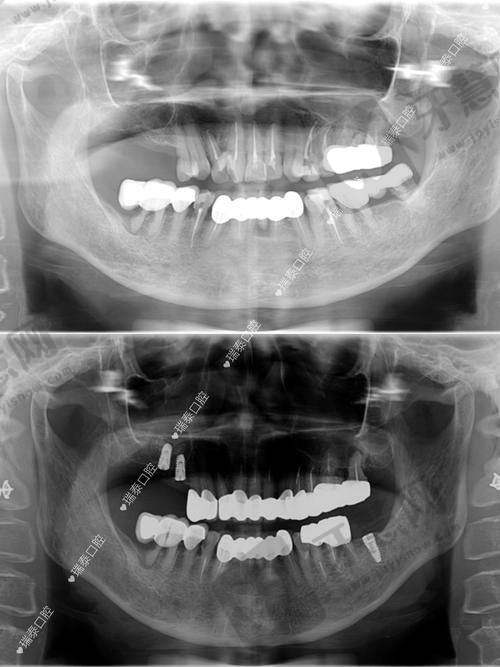

七、北京欢乐菲凡口腔门诊部顾客实例

北京欢乐菲凡口腔门诊部在当地口碑良好,众多患者对服务和治疗成效高度评价。以下是两则顾客实例评价:

顾客A:“我之前牙齿排列不整齐,想矫正又怕影响美观。到欢乐菲凡口腔门诊部后,医生推荐隐形正畸方案。矫正过程舒适,几乎感觉不到矫治器。医生和护士耐心,每次复诊详细沟通牙齿情况。现在牙齿整齐美观,感谢他们。”

顾客B:“我因牙齿缺失来做种植牙,医生技术不错,种植过程顺利,术后修复快。现在种植牙跟真牙一样,咀嚼功能修复好。门诊部环境干净整洁,服务周到,以后看牙就选这里。”